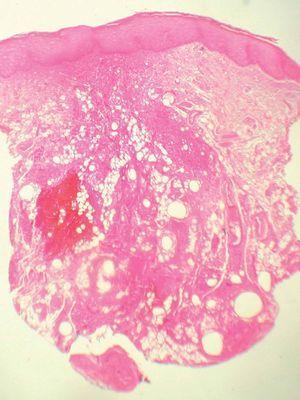

Se le realizó una biopsia en sacabocados de 6 mm de la lesión. La tinción con hematoxilina-eosina fue diagnóstica (figs. 2 y 3).

Fig. 2.--Infiltrado inflamatorio que rodea vacuolas translúcidas. (Hematoxilina-eosina, x20.)

Se observaba un denso infiltrado inflamatorio que se extendía desde la dermis media hasta al tejido celular subcutáneo, rodeando estructuras vacuolazas claras, variables tanto en la forma como en el tamaño y con apariencia espumosa. El infiltrado inflamatorio estaba formado por células epiteloides, histiocitos, linfocitos y células gigantes multinucleadas (figs. 2 y 3).

Histológicamente la silicona puede encontrarse tanto en el espacio intracelular como extracelular. En este último caso muestra una apariencia espumosa, con muchas vacuolas claras, sin birrefringencia y con formas y tamaños variables. Se encuentran rodeadas por un infiltrado granulomatoso compuesto por histiocitos, linfocitos y células gigantes multinucleadas. Estos nódulos granulomatosos se extienden desde la dermis al tejido celular subcutáneo y están rodeados por bandas de tejido conjuntivo 3. Con frecuencia pueden apreciarse cuerpos asteroides, angulados, translúcidos y birrefringentes en el interior del citoplasma de las células gigantes multinucleadas, que corresponden a impurezas de la silicona. Artecoll® es uno de los mejores materiales de relleno permanente empleados actualmente para la corrección de arrugas y el aumento de labios, debido a sus resultados cosméticos prolongados y a la escasa frecuencia de efectos adversos. Consiste en una suspensión compuesta por el 25 % de microesferas de polimetilmetacrilato (PMMA) de 30 a 40 micras de diámetro y el 75 % de una solución al 3,5 % de colágeno. Sólo el 3 % de casos sufren complicaciones, el 0,1 % de las cuales corresponden a granulomas. Típicamente, los granulomas por Artecoll® aparecen de 6 a 24 meses tras la infiltración. Se puede evitar esta reacción teniendo en cuenta que debe infiltrarse profundamente, entre la dermis y el tejido celular subcutáneo. Los granulomas se producen cuando la inyección es demasiado superficial o cuando se realizan retoques 1-7. En la histología se aprecia un infiltrado granulomatoso dérmico difuso formado por vacuolas redondeadas extracelulares, sin birrefringencia, de tamaño y forma uniforme rodeadas de histiocitos y células gigantes multinucleadas 3.